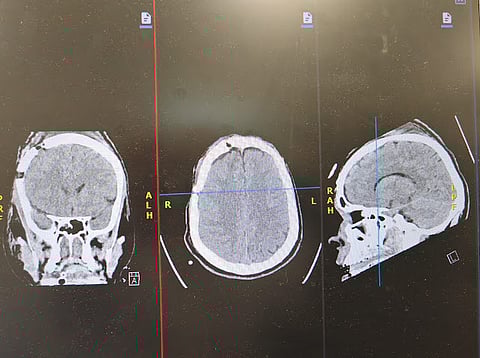

وبيّن التجمع أنه جرى على الفور وضع المستفيد على جهاز التنفس الصناعي، وإجراء الفحوصات الطبية والأشعة اللازمة، التي كشفت عن وجود نزيف حاد فوق الأم الجافية في الجهة الأمامية الصدغية اليمنى، تسبب في انزياح المخ، إلى جانب كسور متعددة في الجمجمة امتدت من أعلى الرأس حتى مقدمته والجيوب الأنفية، وكسور في العظام المحيطة بحجاج العين، إضافة إلى كسر في الفقرتين العنقيتين السادسة والسابعة.

وأضاف تجمع المدينة المنورة الصحي أنه فور تشخيص الحالة جرى تجهيز غرفة العمليات بشكل عاجل، ونُقل المستفيد لإجراء عملية جراحية طارئة لإنقاذ حياته، تم خلالها فتح الجمجمة وتفريغ النزيف من الجهة الأمامية الصدغية اليمنى وصولًا إلى قاع الجمجمة خلف العين اليمنى. واستغرقت العملية ساعتين، تكللت – بفضل الله – بالنجاح، مع السيطرة الكاملة على النزيف.